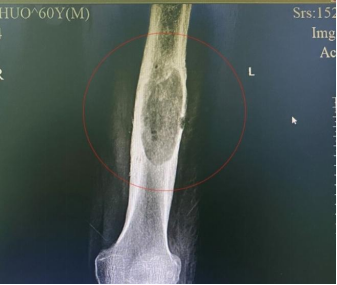

47岁的佛山李女士,5年前摔伤引发右股骨中段骨折,接受“右股骨髓内钉内固定术”后能够恢复行走,但多年来复查仍可见骨折断端间隙,在外院经过髓内钉动力化(拆除近端锁定钉)、拆除近端动力钉..